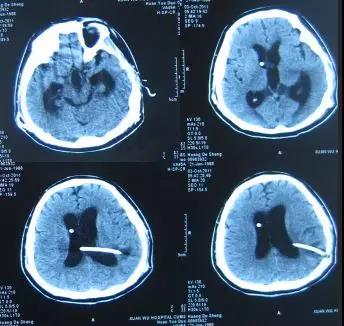

患者于2003年3月1日即15岁时,突发头痛,疼痛难忍,就诊于山东省菏泽市某医院,头部MRI检查诊断为“脑积水”(片子丢失),经保守治疗后症状仍无改善,于2003年4月20日进行了第1次右侧脑室-腹腔分流术,术后6天即2003年4月26日,头痛基本消失,复查头部CT:一侧脑室缩小(图-1),随后出院。

图-1:2003年4月26日头部CT